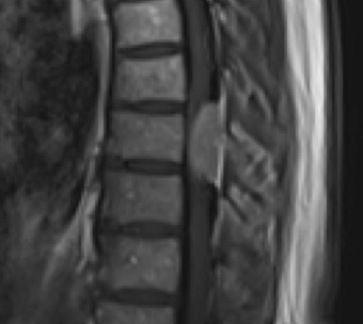

Postoperative MRI T2 illustrating the restoration of CSF surrounding the cord (blue arrow)

Postoperative MRI T1w demonstrating a gross total resection